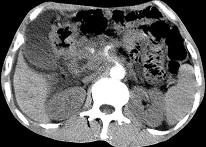

问题 女,50岁,中上腹疼痛,消瘦乏力,影像检查如下图,最佳的诊断是 ( )

选项 A.慢性胰腺炎 B.急性胰腺炎 C.胰腺癌并腹膜后淋巴结转移 D.胰岛素瘤 E.腹膜后淋巴瘤

答案 C